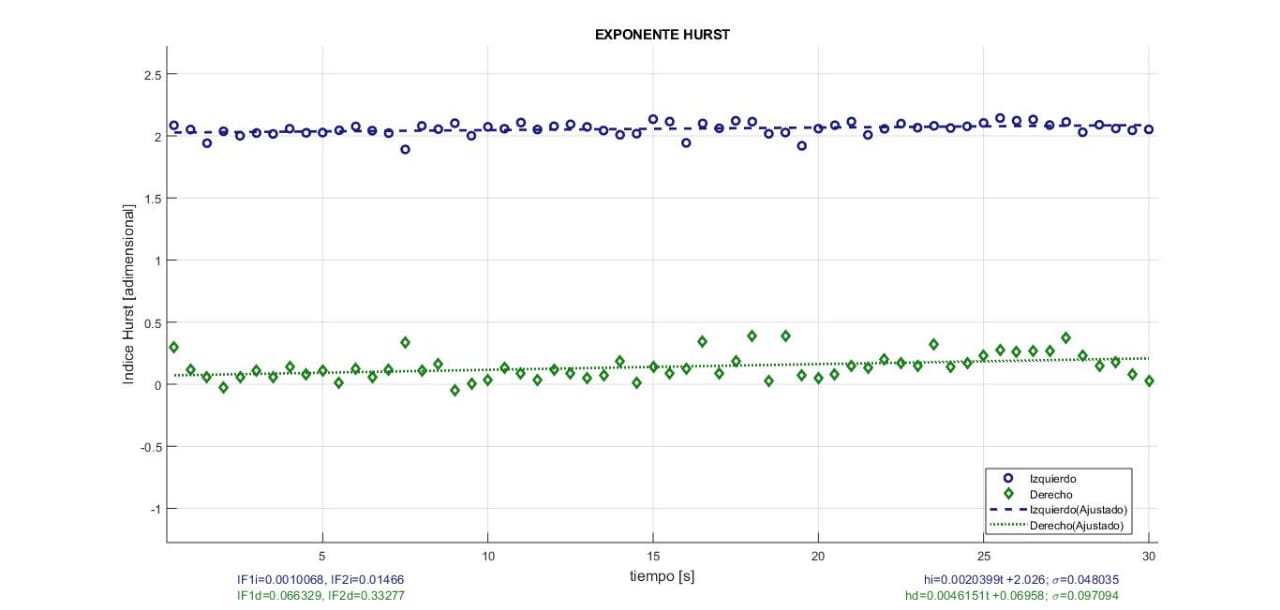

Indice de Hurts de señal EMGS cruda registrada durante contracción isométrica en oclusión centrica (OC), (Laboratorio de fisiología oral, 2019)